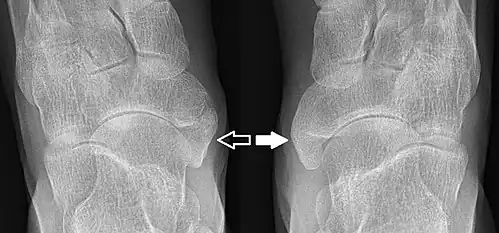

Type 2 sur un pied (flèche sombre) et type 3 sur l'autre (flèche blanche)